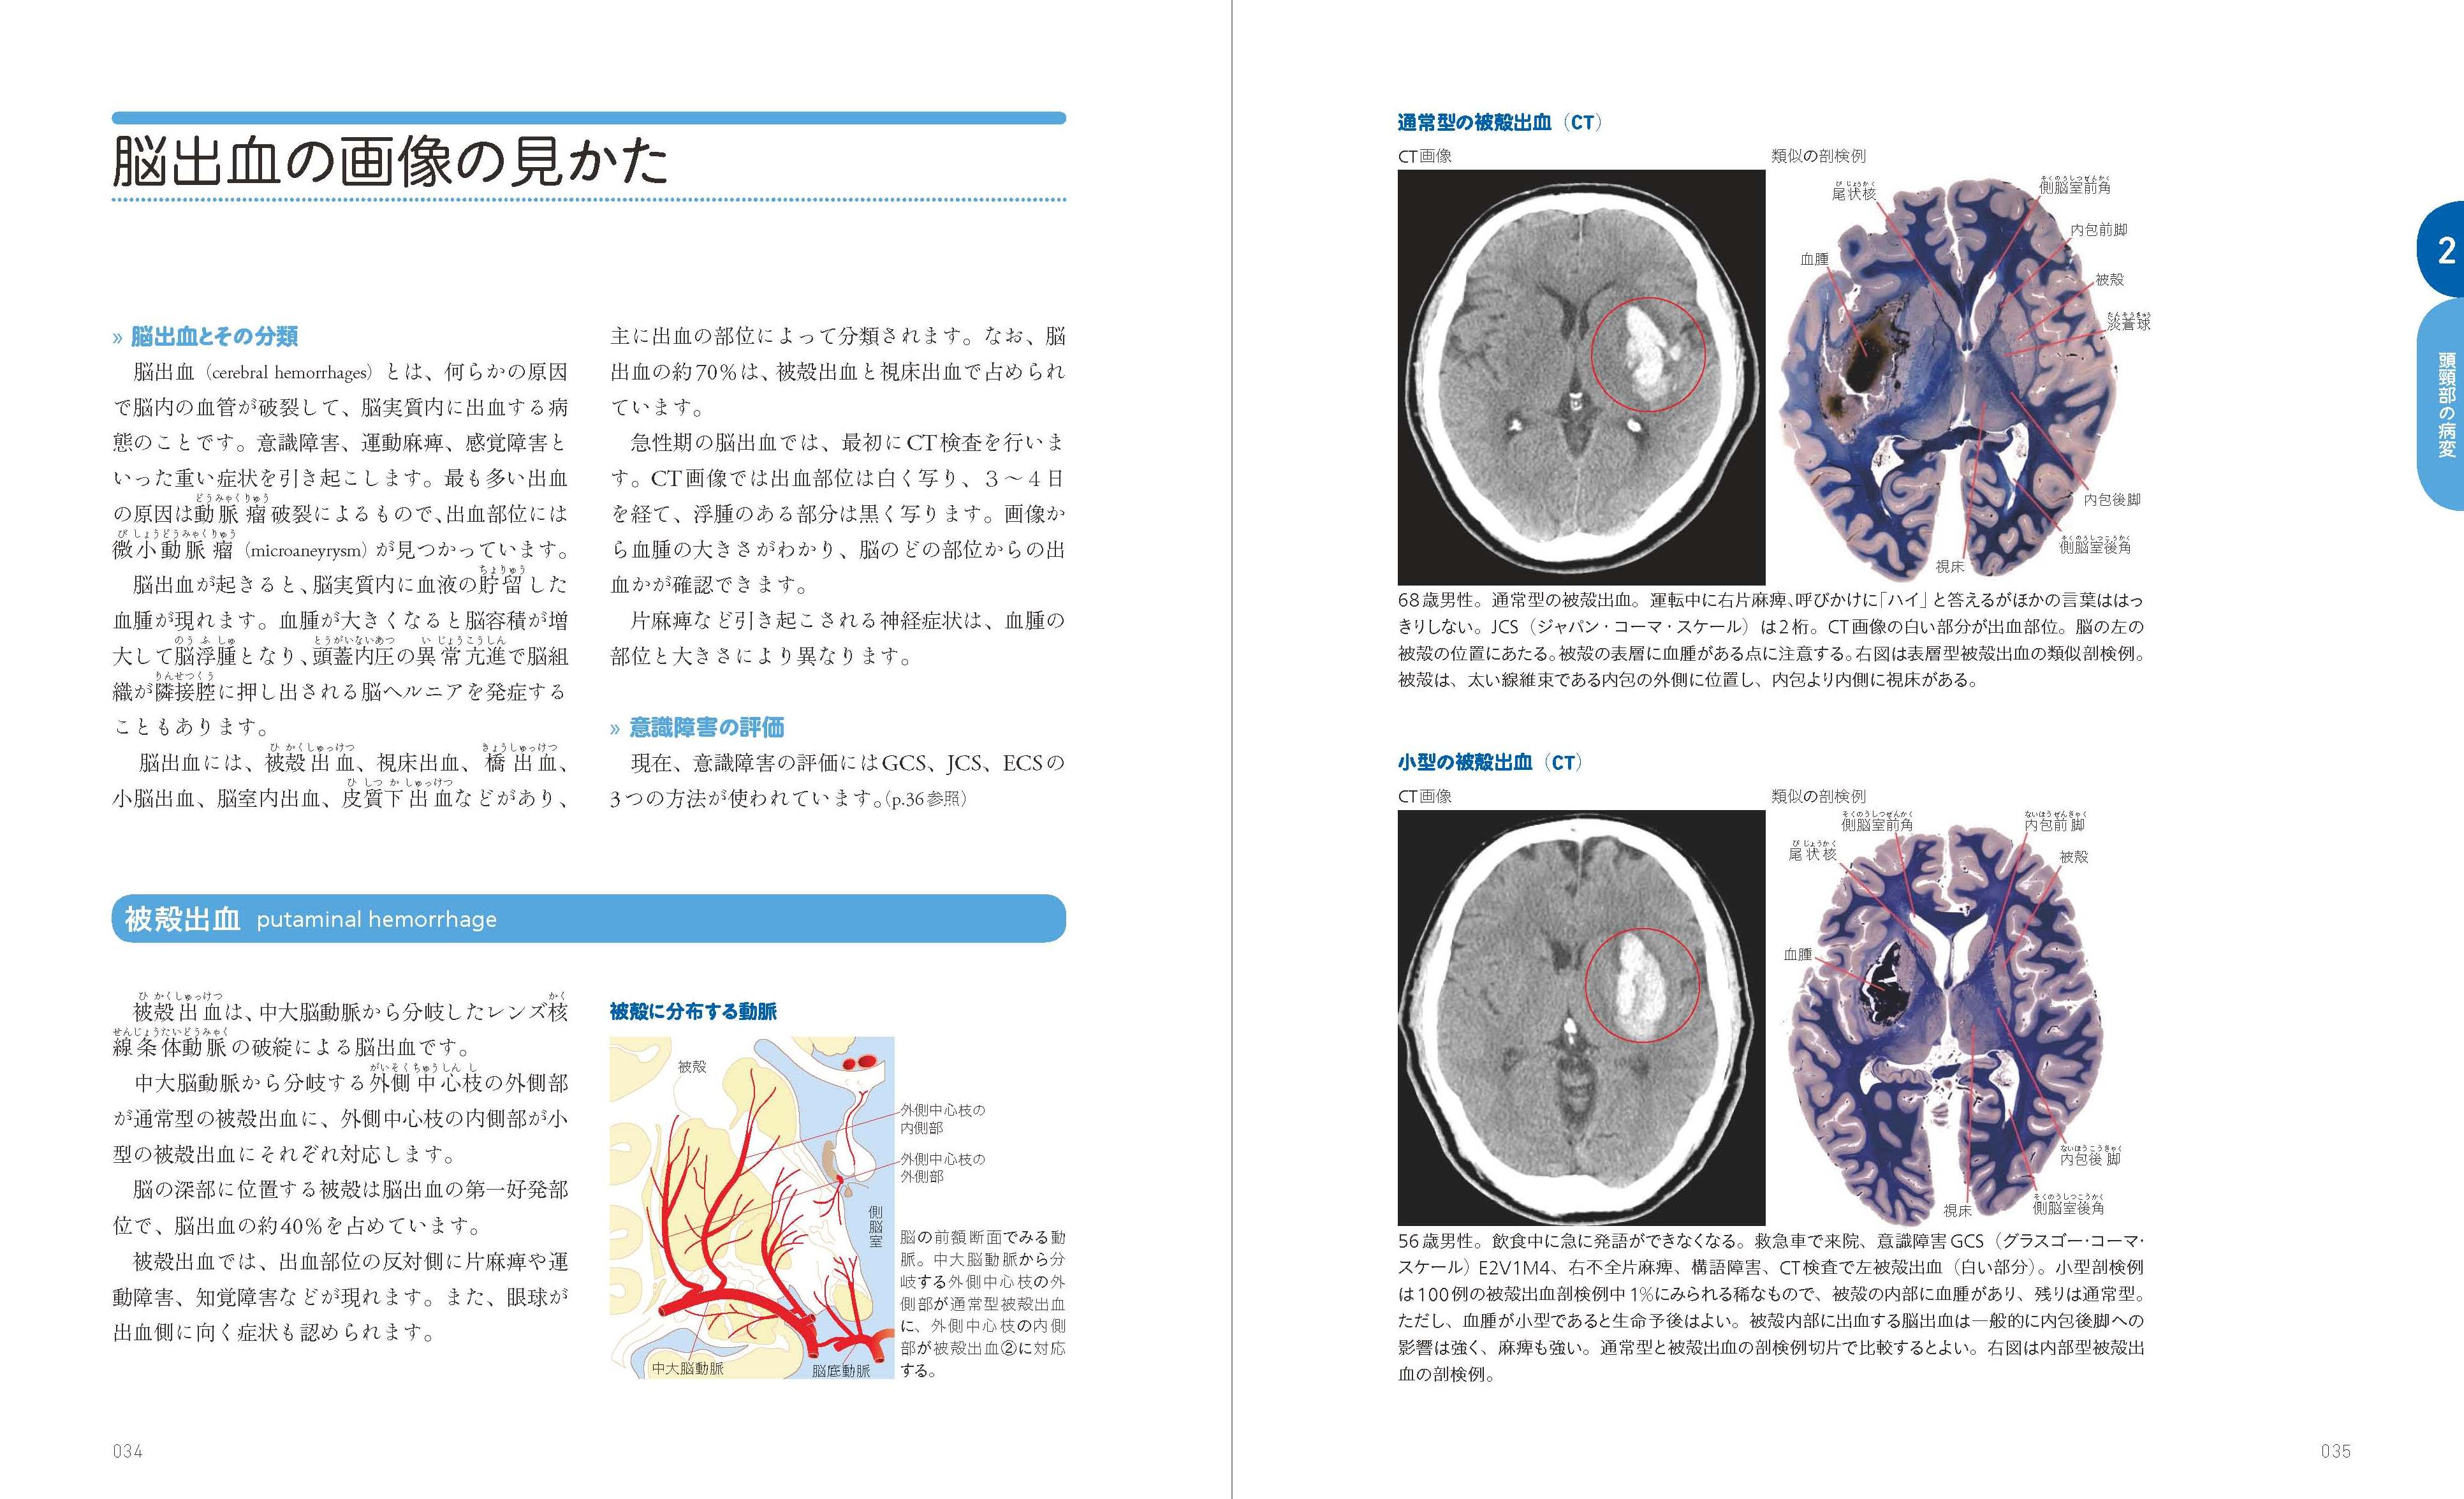

【現品限り一斉値下げ!】 X-Knowledge X線・CT・MRI・PET コメディカルのための画像の見かた | 健康・医学

【現品限り一斉値下げ!】 X-Knowledge X線・CT・MRI・PET コメディカルのための画像の見かた | 健康・医学

X-Knowledge | コメディカルのための画像の見かた X線・CT・MRI・PET。メジカルビュー社|臨床画像特集一覧|臨床画像 2025年5月号。メジカルビュー社|臨床画像特集一覧|臨床画像 2023年6月号。メジカルビュー社|臨床画像 2021年リニューアル。

「コメディカルのための疾患・画像ファイル 臨床技術に活かす画像所見リファレンス」鈴木正行定価: ¥ 5,170

「コメディカルのための疾患・画像ファイル 臨床技術に活かす画像所見リファレンス」鈴木正行定価: ¥ 5,170